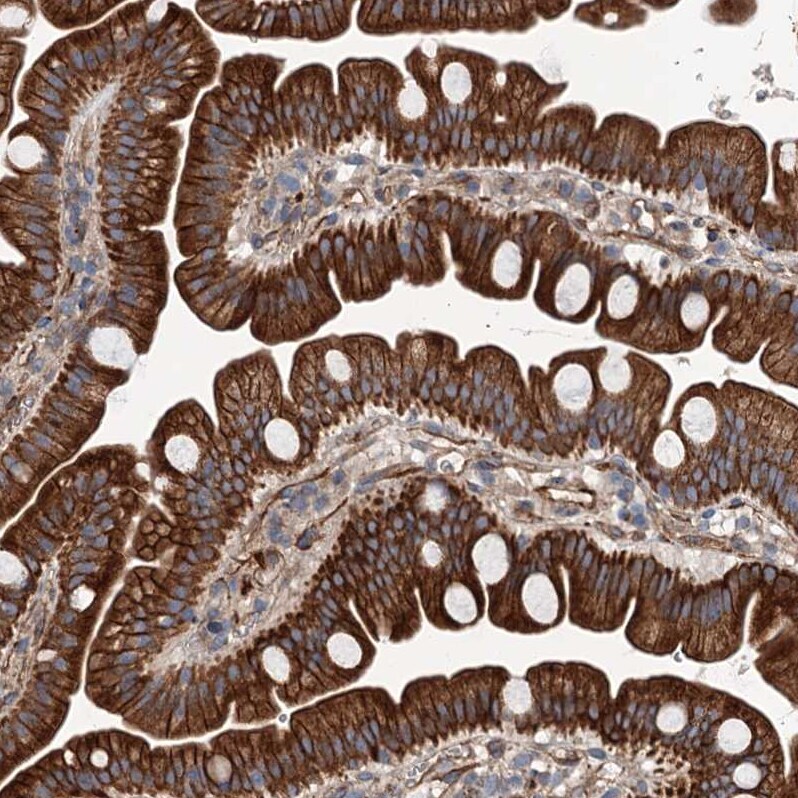

Supportive validation

- Submitted by

- Invitrogen Antibodies (provider)

- Main image

- Experimental details

- Immunohistochemical analysis of NMRAL1 in human small intestine using NMRAL1 Polyclonal Antibody (Product # PA5-59530) shows strong cytoplasmic and membranous positivity in glandular cells.